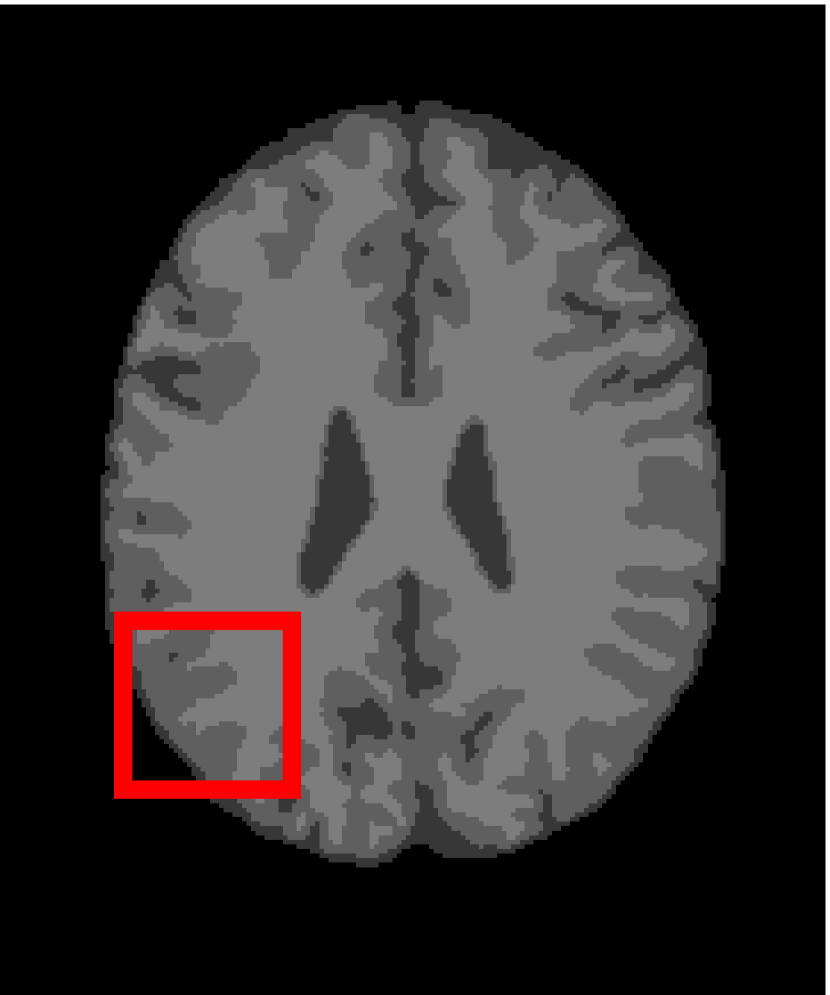

Next, we representatively segment five medical images from BrianWeb. They are represented as five slices in the axial plane with a sequence of 70, 80, 90, 100 and 110, which are generated by T1 modality with slice thickness of 1mm resolution, 9% noise and 20% intensity non-uniformity. Here, we set c=4𝑐4c=4 for all cases. The comparison between WRFCM and its peers are shown in Fig. 9 and Table II. The best values are in bold.

Figure 9: Segmentation results on five medical images. The parameter: ϕ=5.35italic-ϕ5.35\phi=5.35. From top to bottom: noisy images, ground truth, and results of FCM_S1, FCM_S2, FLICM, KWFLICM, FRFCM, WFCM, DSFCM_N, and WRFCM.

By a view of the marked red square in Fig. 9, we find that FCM_S1, FCM_S2, FLICM, KWFLICM and DSFCM_N are vulnerable to noise and intensity non-uniformity. They give rise to the change of topological shapes to some extent. Unlike them, FRFCM and WFCM achieve sufficient noise removal. However, they produce overly smooth contours. Compared with its seven peers, WRFCM can not only suppress noise adequately but also acquire accurate contours. Moreover, it yields the visual result closer to ground truth than its peers. As Table II shows, WRFCM obtains optimal SA, SDS and MCC results for all five medical images. As a conclusion, it outperforms its peers visually and quantitatively.